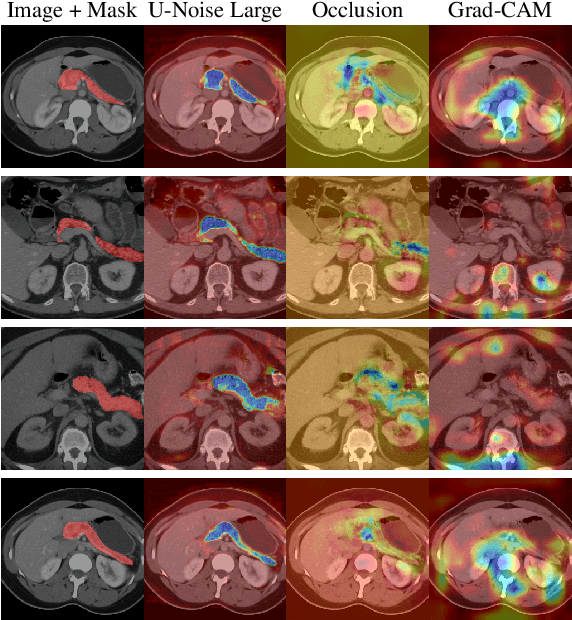

Abstract:Deep Neural Networks (DNNs) are widely used for decision making in a myriad of critical applications, ranging from medical to societal and even judicial. Given the importance of these decisions, it is crucial for us to be able to interpret these models. We introduce a new method for interpreting image segmentation models by learning regions of images in which noise can be applied without hindering downstream model performance. We apply this method to segmentation of the pancreas in CT scans, and qualitatively compare the quality of the method to existing explainability techniques, such as Grad-CAM and occlusion sensitivity. Additionally we show that, unlike other methods, our interpretability model can be quantitatively evaluated based on the downstream performance over obscured images.